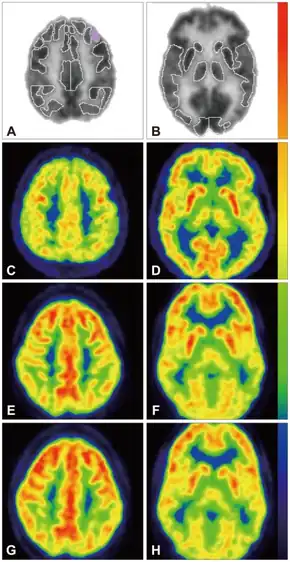

In 1997, a small pilot study was published on the efficacy of tetrahydrobiopterin (BH4) on relieving the symptoms of autism, which concluded that it "might be useful for a subgroup of children with autism" and that double-blind trials are needed, as are trials which measure outcomes over a longer period of time.[28] In 2010, Frye et al. published a paper which concluded that it was safe, and also noted that "several clinical trials have suggested that treatment with BH4 improves ASD symptomatology in some individuals."[29]

- ↑ Fernell E, Watanabe Y, Adolfsson I, Tani Y, Bergström M, Hartvig P, et al. (May 1997). "Possible effects of tetrahydrobiopterin treatment in six children with autism--clinical and positron emission tomography data: a pilot study". Developmental Medicine and Child Neurology. 39 (5): 313–8. doi:10.1111/j.1469-8749.1997.tb07437.x. PMID 9236697. S2CID 12761124.